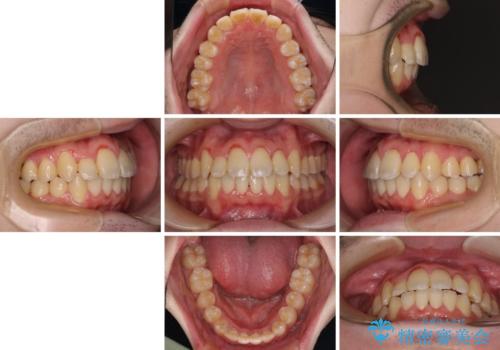

全顎的なクロスバイト 補助装置を用いてワイヤー矯正

- 八重歯や奥歯の噛みにくさを気にして来院された患者様です。

前歯のクロスバイトや八重歯の他に、左右最後臼歯のシザーズバイト(鋏状咬合)が認められました。

シザーズバイト改善のために補助装置を使用しながら、ワイヤー装置にて全体の歯列を整えることとしました。

シザーズバイトは強く咬合する奥歯を移動させるため、多くの場合においてワイヤー矯正の装置のみでは改善が困難となります。

奥歯の咬み合わせ改善は治療初期からしっかりとアプローチする必要があるため、補助装置を積極的に利用します。